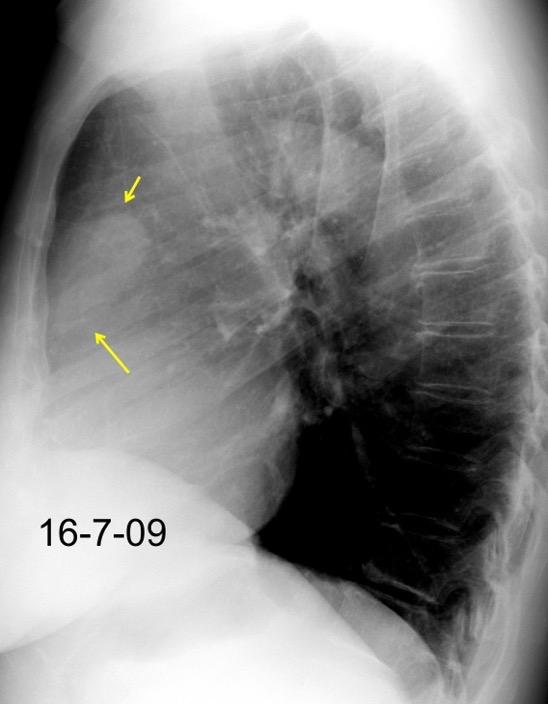

30 años

Borramiento de la banda PARA-aórtica por AdenoCa. de LII, no visible en 2005

Colapso de LII. TC: secreciones bronquiales.

Endoscopia tapón mucopurulento extraído

Borramiento parcial por Ca. epidermoide.